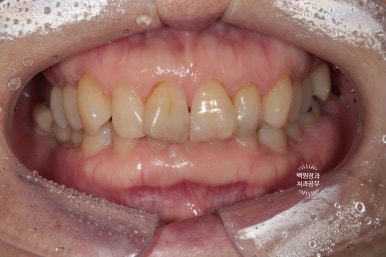

좌측이 3년 전, 우측이 3년 후 입니다.

저희 치과의 카메라가 달라져 비록 같은 색감을 내고 있지는 않으나, 2차 충치나 크라운의 파절 없이 깔끔하게 유지되고 있는 앞니 지르코니아 크라운들을 보실 수 있습니다!!

좌측과 우측 측면에서 보아도 아주 깔끔하게 유지되고 있는 앞니 지르코니아 크라운들입니다.

매우 흡족한 결과입니다 :)

3년이 지나니 상악동 뼈이식술을 했던 곳은 이제 거의 내 뼈와 하나가 된 것처럼 예쁘게 성숙된 모습을 보여주고 있고, 앞니 지르코니아 크라운은 꼼꼼히 관리해주신 덕분에 충치 하나 없이 신경치료 하지 않았음에도 아주 잘~ 쓰고 있는 모습을 확인할 수 있었습니다!